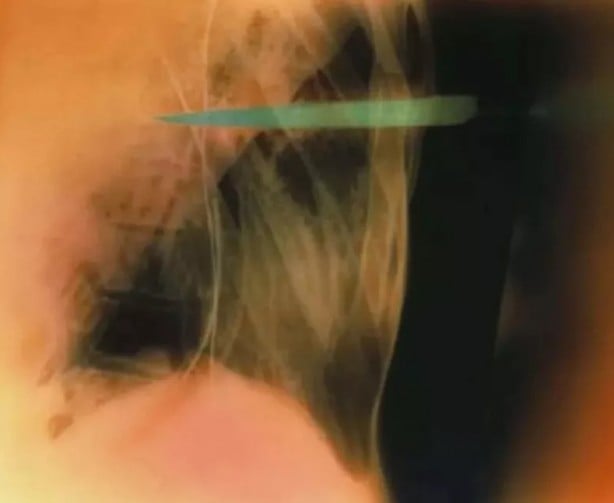

Bir kadının boğazında görüntülenen çengelli iğnenin renkli röntgeni...